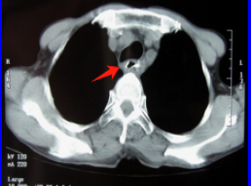

治疗前 病灶占据整个食管管腔 治疗后 食管病灶已完全消失

针对王大爷的病情及王先生的疑虑,医院组织放疗科、肿瘤内科专家为其会诊,详细解释了放疗的治疗原理、流程和反应,彻底打消了王先生的顾虑,王先生为父亲选择了“根治性精准放射治疗+局部热疗”的治疗方案。经过一个多月的放疗,王大爷吞咽越来越顺畅,饭量逐渐恢复到正常,体重也增加了。治疗中期复查CT,病灶缩小了一大半,这更加坚定了他们战胜病魔的信心。放疗结束后,王大爷还在医生的鼓励下,做了4个周期的全身化疗巩固。今天是他们返院复查的日子。